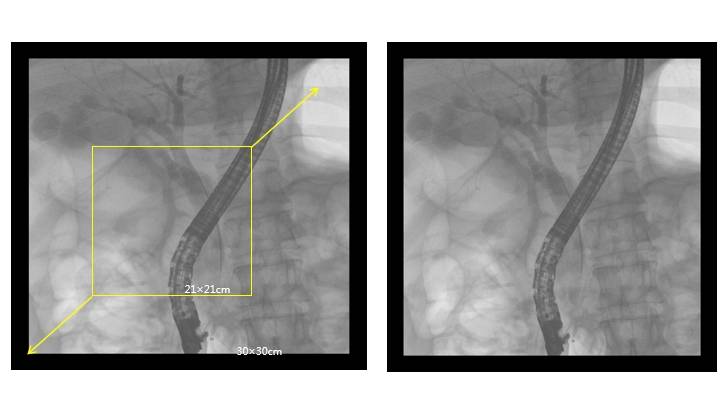

高端介入平板C形臂PLX7100A——ERCP臨床圖像:

介入平板C形臂PLX7100A圖像

廣闊視野:30cm×30cm的成像面積,能夠一次性全面覆蓋胸、腹、盆腔,減少了多次曝光和輻射的風(fēng)險(xiǎn),同時(shí)避免了檢查中的重疊和遺漏。

大尺寸平板探測(cè)器,成像面積提高一倍以上